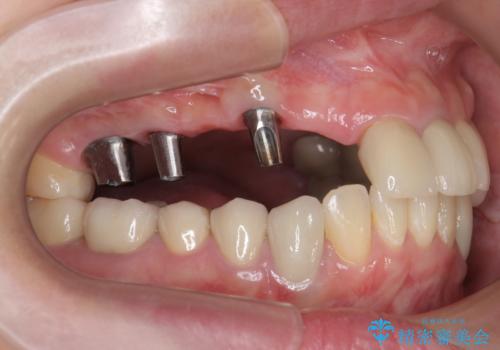

多数の歯が失われておりブリッジは行えないような状況で、インプラント治療か入れ歯治療かを提案しインプラント治療を希望・選択されました。

- 120万円(ストローマンインプラント×3・骨造成・チタンカスタムアバットメント×3・フルジルコニアクラウン×5)費用は治療当時の料金となります